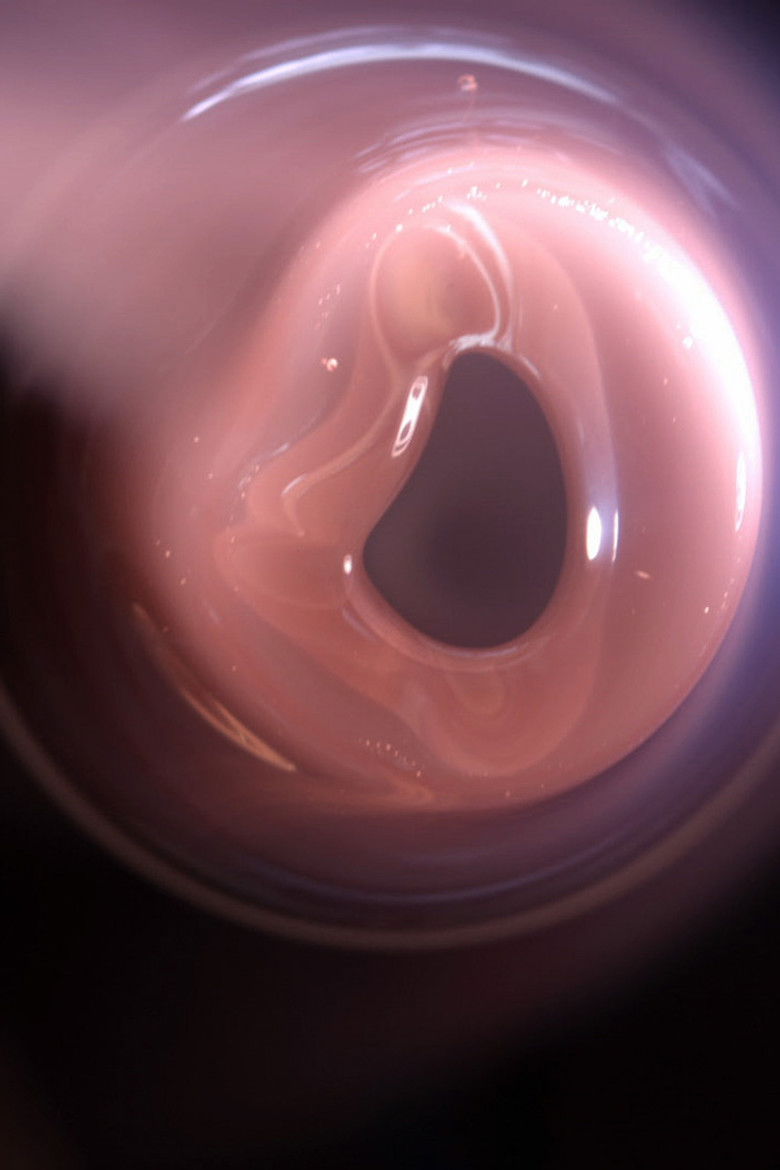

Haptic Skins of a Glass Eye